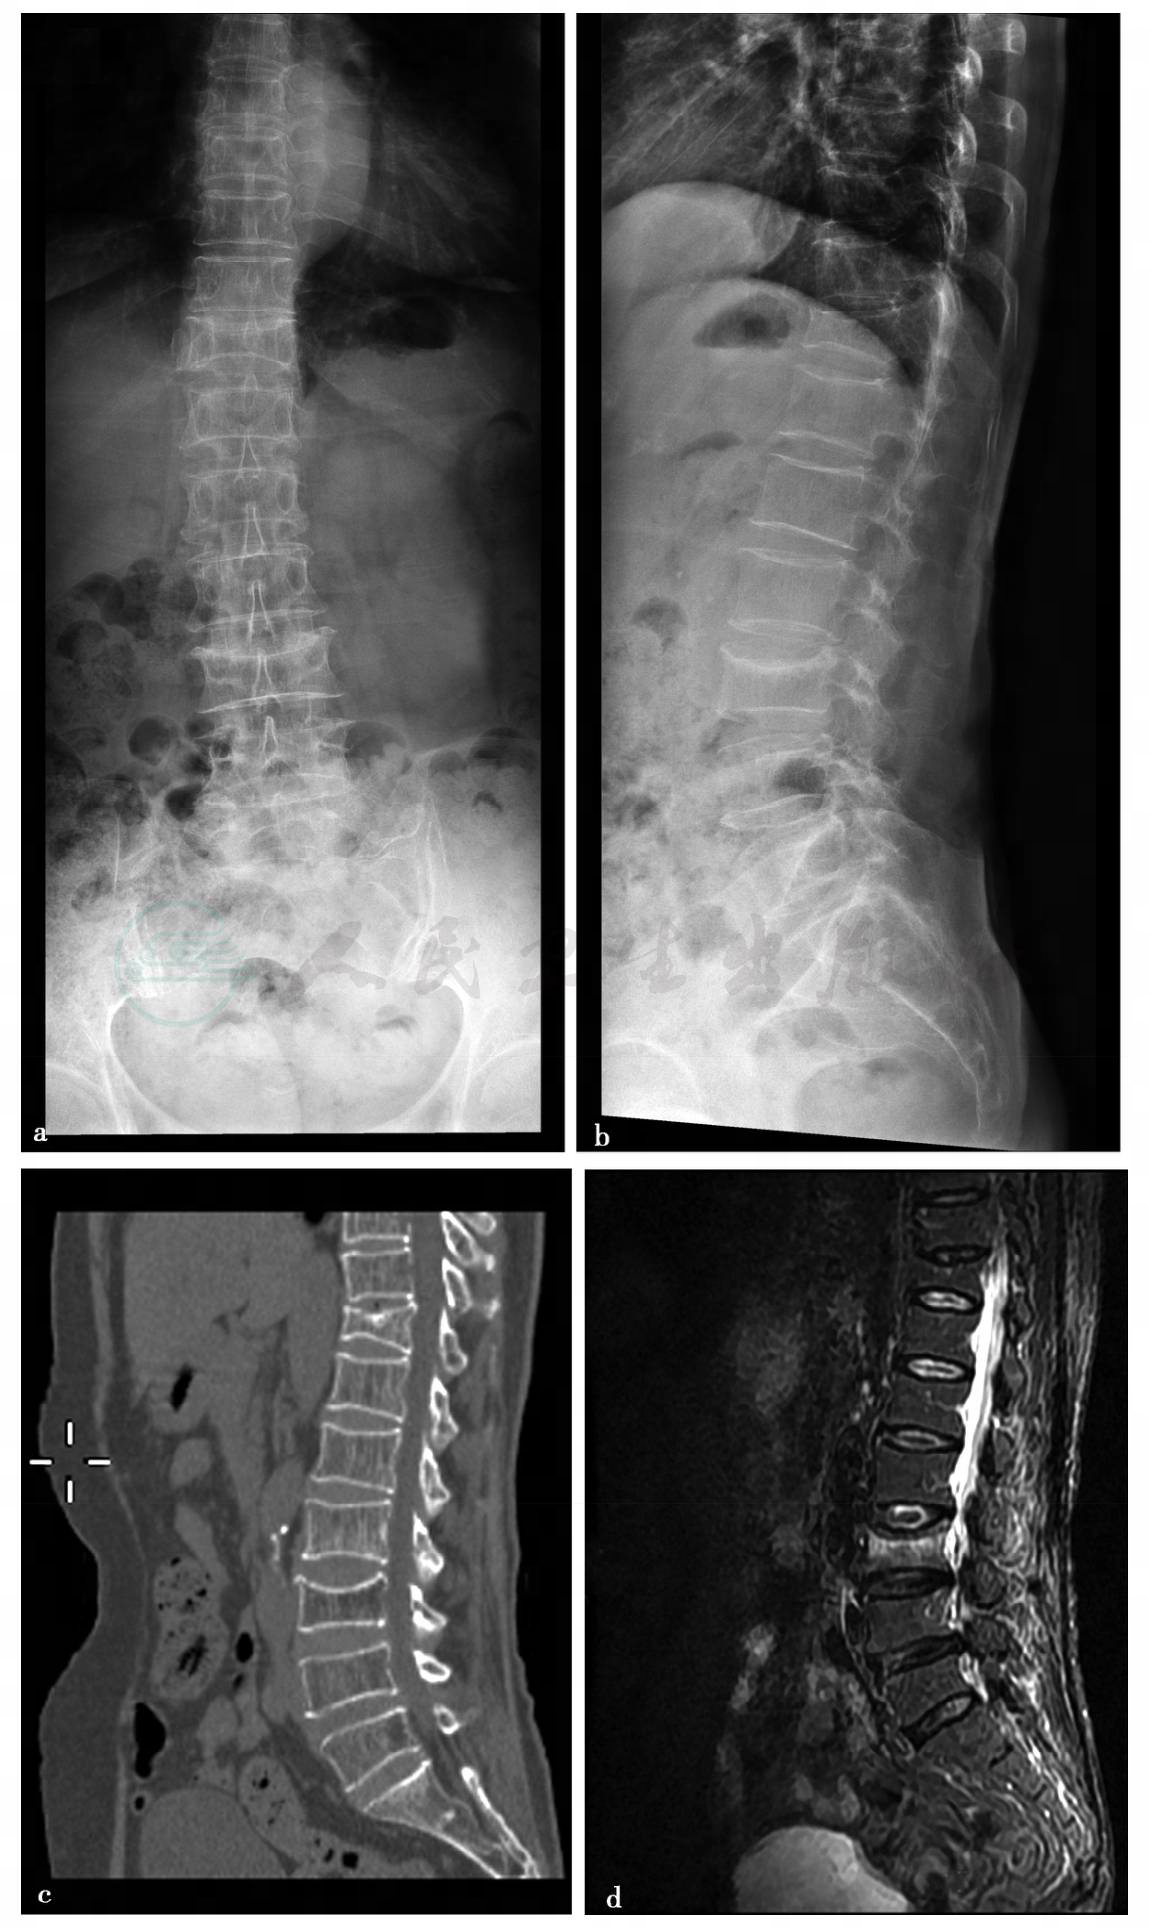

病例2,女性,58岁,背部疼痛。

病例2:X线及CT平扫。

图1 图1a、b,腰椎正侧位T12椎体楔形变,L4椎体终板凹陷。图1c,腰椎CT平扫矢状位、冠状位三维重建。图1d,腰椎MRI(FST2WI)示T12椎体内未出现水肿信号,为陈旧骨折,L4椎体内见水肿信号,为新鲜骨折

病例2,骨质疏松症、椎体压缩骨折。